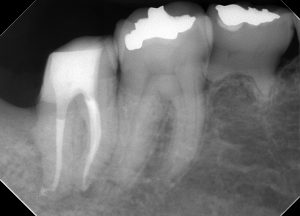

(1年経過後のレントゲン、CT)

いかなる症状もなく、周囲の骨の再生を認める。

補綴物の適合も問題ない。

噛むことも問題なく、完治と言えるだろう。

根管治療に限らず、虫歯治療においても、一つ一つの治療の精度が予後に影響することが分かる症例だと言えよう。